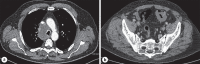

The colon is an uncommon secondary site for metastasis of lung adenocarcinoma. Distinguishing primary colonic carcinoma from metastatic spread of lung carcinoma can be difficult. We present a case of a patient with lung adenocarcinoma who, on abdominal computed tomography scan examination, was found to have a sigmoid tumor that was thought to represent a synchronous primary colorectal adenocarcinoma. Histological examination of endoscopic sigmoid tumor biopsies confirmed this to be metastasis from the lung adenocarcinoma. The patient subsequently developed major rectal bleeding and deteriorated significantly. This case also illustrates the poor prognosis association with colorectal metastasis of lung cancer.